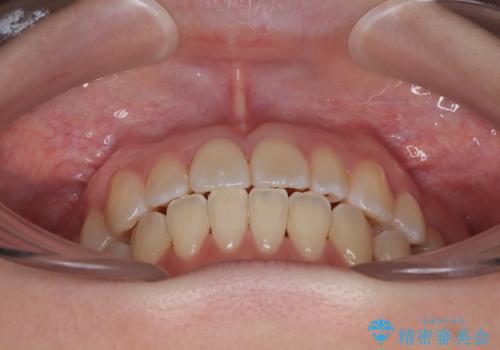

- 20代女性

- 患者様は「歯並び全体のデコボコが気になり、人前で笑うことに抵抗がある」とのことでご来院されました。

診査の結果、上下顎ともに叢生が認められましたが、ワイヤー矯正・マウスピース矯正のいずれでも対応可能な症例でした。